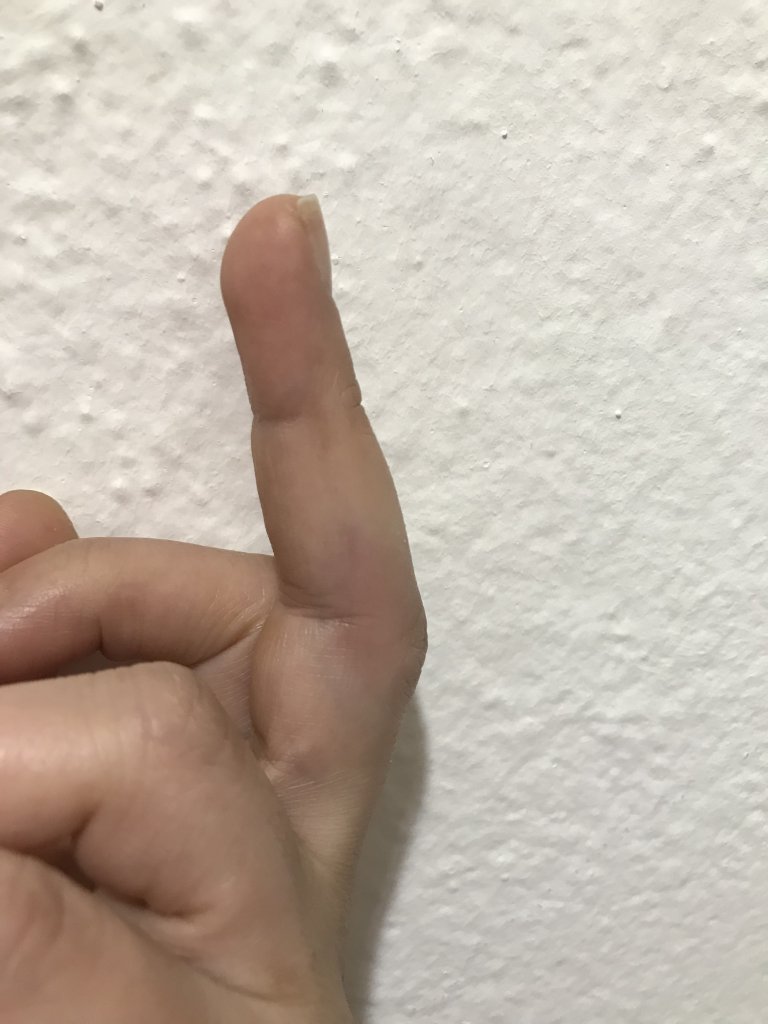

Eşim le voleybol oynarken topa nasıl vurdum bilmiyorum parmağım burkuldu mu çarptı mı döndü mü anlamadım ağrımaya başladı daha sonra kızarıklık şişme oluştu sabah acil servise gittim röntgen çekti acil Dr kırık çatlak yok dedi atel taktı ağrı kesici buz komplesi krem yazdı işe geldim ancak parmak git gide şişiyor ve hareket muhtemelen şişlikten dolayı sınırlanıyor anlamamış olabilir mi Dr sanmıyorum ama tendon diye bişey duydum ilk defa ne olduğunu da anlamadım röntgen de anlaşılmaz mıydı doku zedelenmesi daha önce yaşadım elim de çatladı ayağımda kırıldı  herşey başıma gelmiş şaka gibi böyle şişmedi hiç bu durumu yaşayan var mı aramızda yada benzer bişey aşma aşama resim ekledim ultrason anlayan vardır diye onu da koydum

herşey başıma gelmiş şaka gibi böyle şişmedi hiç bu durumu yaşayan var mı aramızda yada benzer bişey aşma aşama resim ekledim ultrason anlayan vardır diye onu da koydum